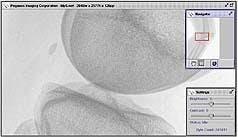

FIGURE 1. Using wavelet compression, a server stores a minimum-resolution image and compresses the additional data using a wavelet transform. The server then sends the minimum-resolution picture immediately and fills in the picture over time until either the user decides on an acceptable resolution or receives the entire image file. In the knee x-ray, the small thumbnail (far right), indicates the region of interest. The Pegasus software requests coefficients for pixels in the region of interest and then fills in the additional details outside the region of interest.